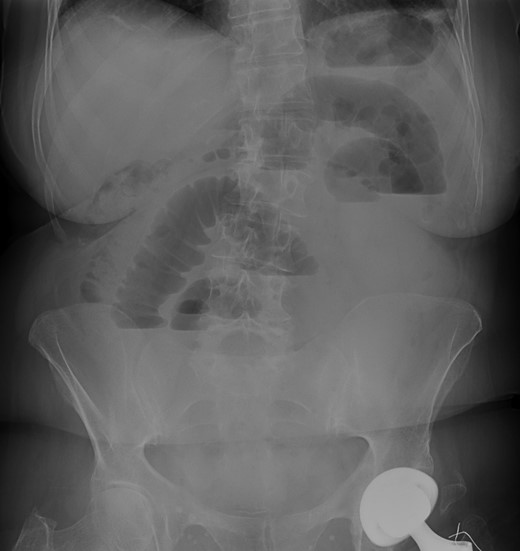

Blood tests were within normal limits except for an elevated serum creatinine of 1.3 mg/dl and C-reactive protein of 2.4 mg/dl. The abdominal X-rays showed small bowel distension with air fluid levels (Fig. 1). An abdominal computed tomography (CT) scan was performed diagnosing small bowel obstruction secondary to an incarcerated hernia in the left upper abdominal wall. The hernia defect lied through the internal oblique and transversus abdominis muscles aponeurosis with its sac extending posterior to the left rectus abdominis. There weren´t signs of intestinal ischemia (Figs 2 and 3).

Abdominal X-rays—small bowel distension with air fluid levels.